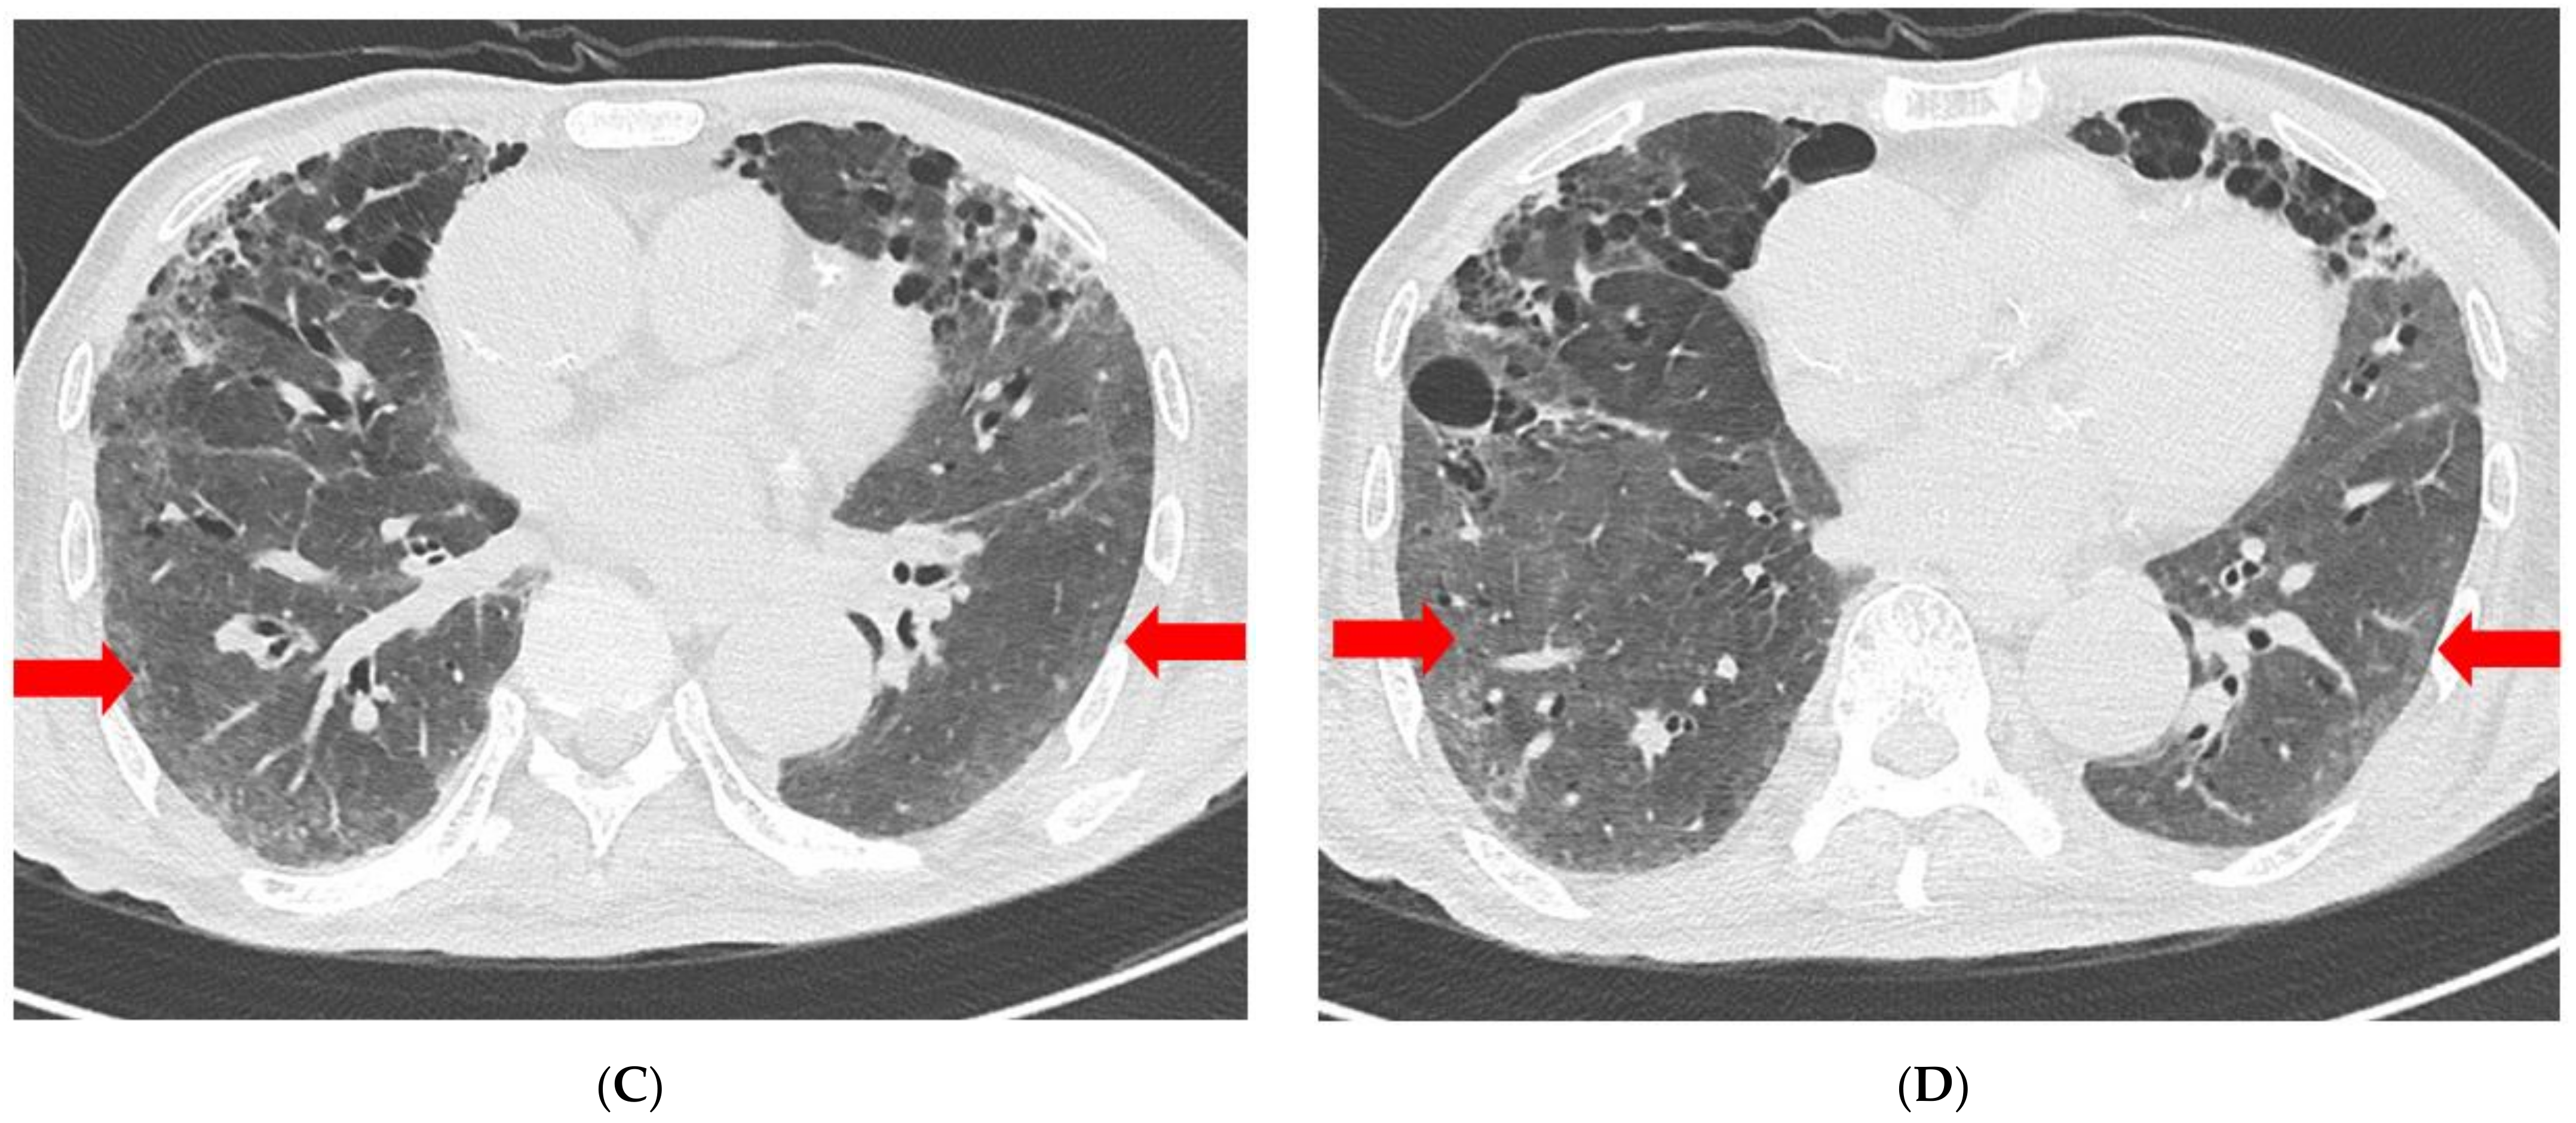

| Chest radiography | GGO in BLLF | Increased GGO | Increased GGO | Decreased GGO | Decreased GGO | Decreased GGO | No interval change | No interval change |